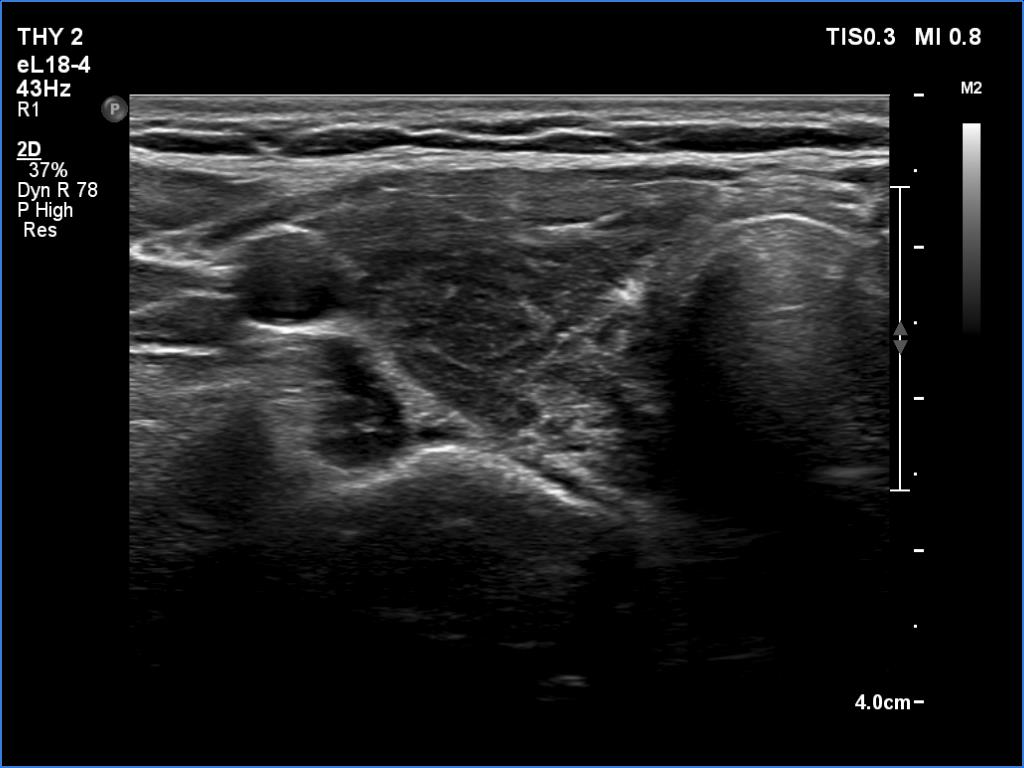

Second examination a year later (second row of images):

Comment. The patient presented a post partum thyroiditis, i.e., the underlying autoimmune thyroiditis became more active. The change in ultrasound pattern is also in line with this. Be aware the rapid change in ultrasound pattern. In other cases, the echogenicity can change in years, rather decades in the case of a hypothyroidism. The structure is expected to show the pattern seen in the first study a year later.Clinical data: Half a year ago, the patient gave birth. She took 100 microgram of medicine a day in the second half of the pregnancy, and after giving birth she returned to the previously used dose of 50 micrograms a day. She gained 8 kg in the last three months and had other symptoms which suggested underdosing.

Palpation: unchanged.

Laboratory tests: TSH 9.88 mIU/L, FT4 7.61 pM/L on daily 50 microgram levothyroxine.

Ultrasonography. In contrast to the previous examination, the entire thyroid became hypoechoic. There were only small islets with less hypoechoic pattern.

Suggestion: to increase the dose of levothyroxine to daily 75 micrograms. Repeat TSH in 6 months.